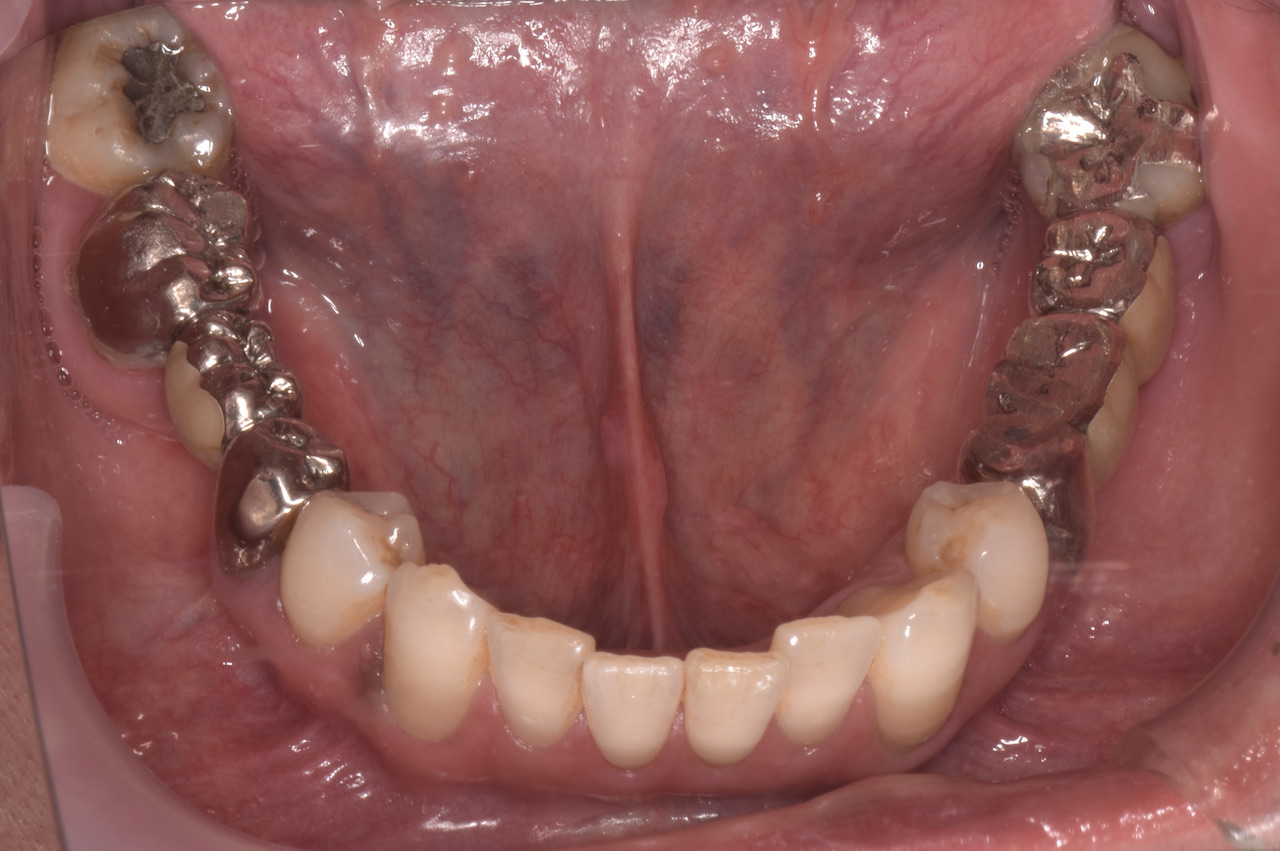

全顎的に複数の治療部位で、インプラント・ブリッジ・ダイレクトボンディング・セラミッククラウンなど、適切な治療方法を組み合わせて包括的な治療を進めました。

治療を終えた「T-scan」による咬合調整後の患者さんの感想を伺うと「とても良く咬め、インプラントが入っていても全く違和感を感じない」という事でした。このようにデジタルで計測される客観的なデータと患者さんこそが一番感じるご自身からの体の声を一体化させる治療が大切です。